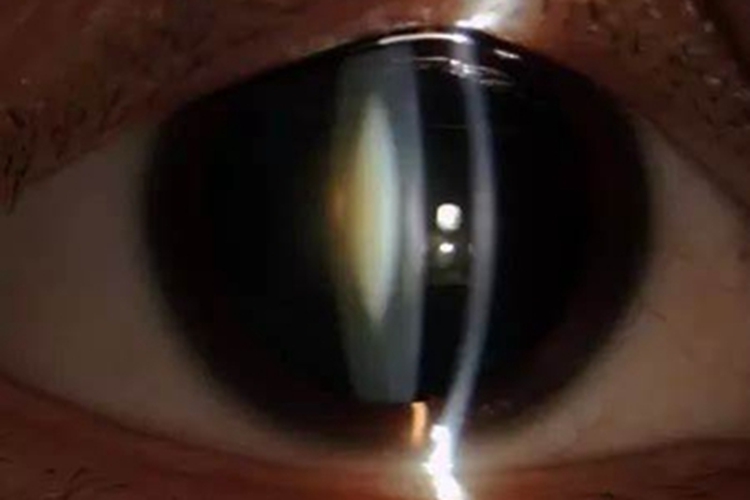

后囊下白内障表现为晶状体后囊膜下浅层皮质出现棕黄色混浊,为许多致密小点组成,其中有小空泡和结晶样颗粒,外观似锅巴状、白斑样。由于混浊位于视轴,所以早期就会出现明显视力障碍。